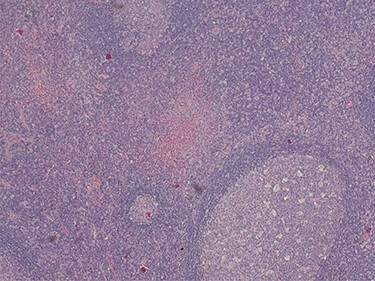

Because of the recent increase in the size of the swelling, the patient presented to our clinic and agreed to undergo excision of the swelling. A well-circumscribed swelling measuring 2.5 cm × 1.5 cm which was soft to firm in consistency was completely excised (Fig. 1). Histopathological examination showed sections of lymph node with florid follicular and germinal center hyperplasia (Fig. 2), and paracortical expansion by plasma cells, small lymphocytes and mast cells (Fig. 3). Marked eosinophilic infiltration with focal micro-abscess formation was present (Fig. 4). The features were consistent with Kimura’s disease. There was no evidence of malignancy. At 6 months follow-up, the patient had no evidence of recurrence.

Histopathology of the lymph node showing an eosinophilic micro-abscess. Haematoxylin and Eosin stain. Magnification ×20.